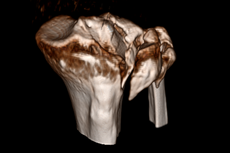

Zur weiterführenden Diagnostik einer Beckenverletzung steht uns modernste radiologische Bildgebung mit 3D-Rekonstruktion zur Verfügung. Auch intraoperativ ist eine 3D-Bildgebung bei laufender Operation möglich. Zur Therapie von vorderen und hinteren Beckenring-Frakturen favorisieren wir Platten-Osteosynthesen offener Reposition, aber auch minimal-invasive Therapieoptionen und transkutane Verschraubungen.

Frakturen der Hüftgelenkspfanne

Frakturen der Hüftgelenkspfanne (Azetabulumfrakturen) sind häufig komplizierte Frakturen. Die Schwierigkeit der Versorgung liegt in der exakten Wiederherstellung der konkaven Gelenkfläche. Auch bei optimaler Versorgung kann sich aus einer Azetabulumfraktur ein frühzeitiger Hüftgelenksverschleiß entwickeln.